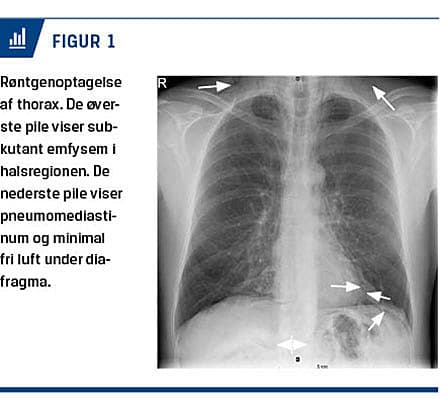

To dage senere henvendte patienten sig til en vagtlæge pga. hæshed, ondt i halsen og en følelse af hævelse af halsmuskulaturen. En røntgenoptagelse af thorax viste subkutant emfysem i halsregionen, pneumo-

mediastinum, fri luft under diafragma på venstre side, men ingen tegn på pneumothorax (Figur 1). Anamne-stisk var der intet forudgående traume. Objektivt var patienten upåvirket. Bilateralt fortil på halsen blev der mærket en knitren, og der blev fundet let krepitation basalt på venstre side ved lungestetoskopi, men han havde ellers vesikulær respiration. Abdomen var fuldstændig upåfaldende. Resultaterne af blodprøver var normale fraset et C-reaktivt protein-niveau på 39 mg/l.